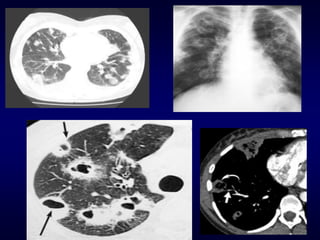

The patient was initially treated for severe

pneumonia and a chest radiography

followed by computed (CT) scan of the chest

were obtained .

On the basis of radiological

findings, what is your diagnosis

1-Septic pulmonary embolism.

2- Cavitating pneumonia.

3- Pulmonary TB

4-Cavitating secondaries